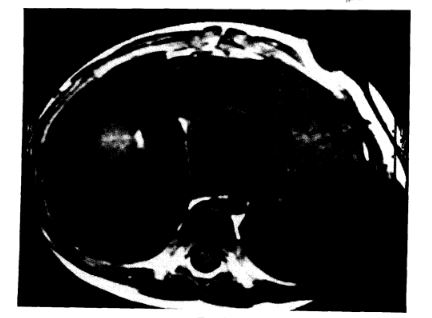

Fibroma de ventrículo izquierdo

IMÁGENES EN CARDIOLOGÍA